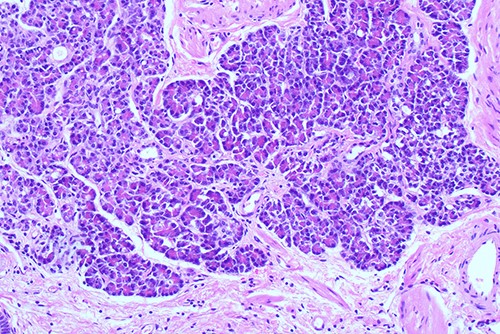

She proceeded to an elective laparoscopic cholecystectomy. At the time of her procedure, she was found to have features suggestive of chronic cholecystitis with peritoneal adhesions. Her procedure was straightforward and intraoperative cholangiogram showed a spiral cystic duct with the trifurcation of intrahepatic ducts. Her common bile duct appeared mildly dilated however tapered at the lower end and showed filling of the duodenum with no filling defects. The histology from the gallbladder showed variable fibromuscular thickening of the wall with intramural cystic Rokitansky-Aschoff sinuses, but no significant inflammation. Focal ectopic pancreatic acinar tissue (1 mm) within the gallbladder was found (Figs 1–3). There was no evidence of intestinal metaplasia, dysplasia or malignancy.

Histological examination of gallbladder ×40 showing island of ectopic pancreatic tissue adjacent to the mucosa of the gallbladder neck.